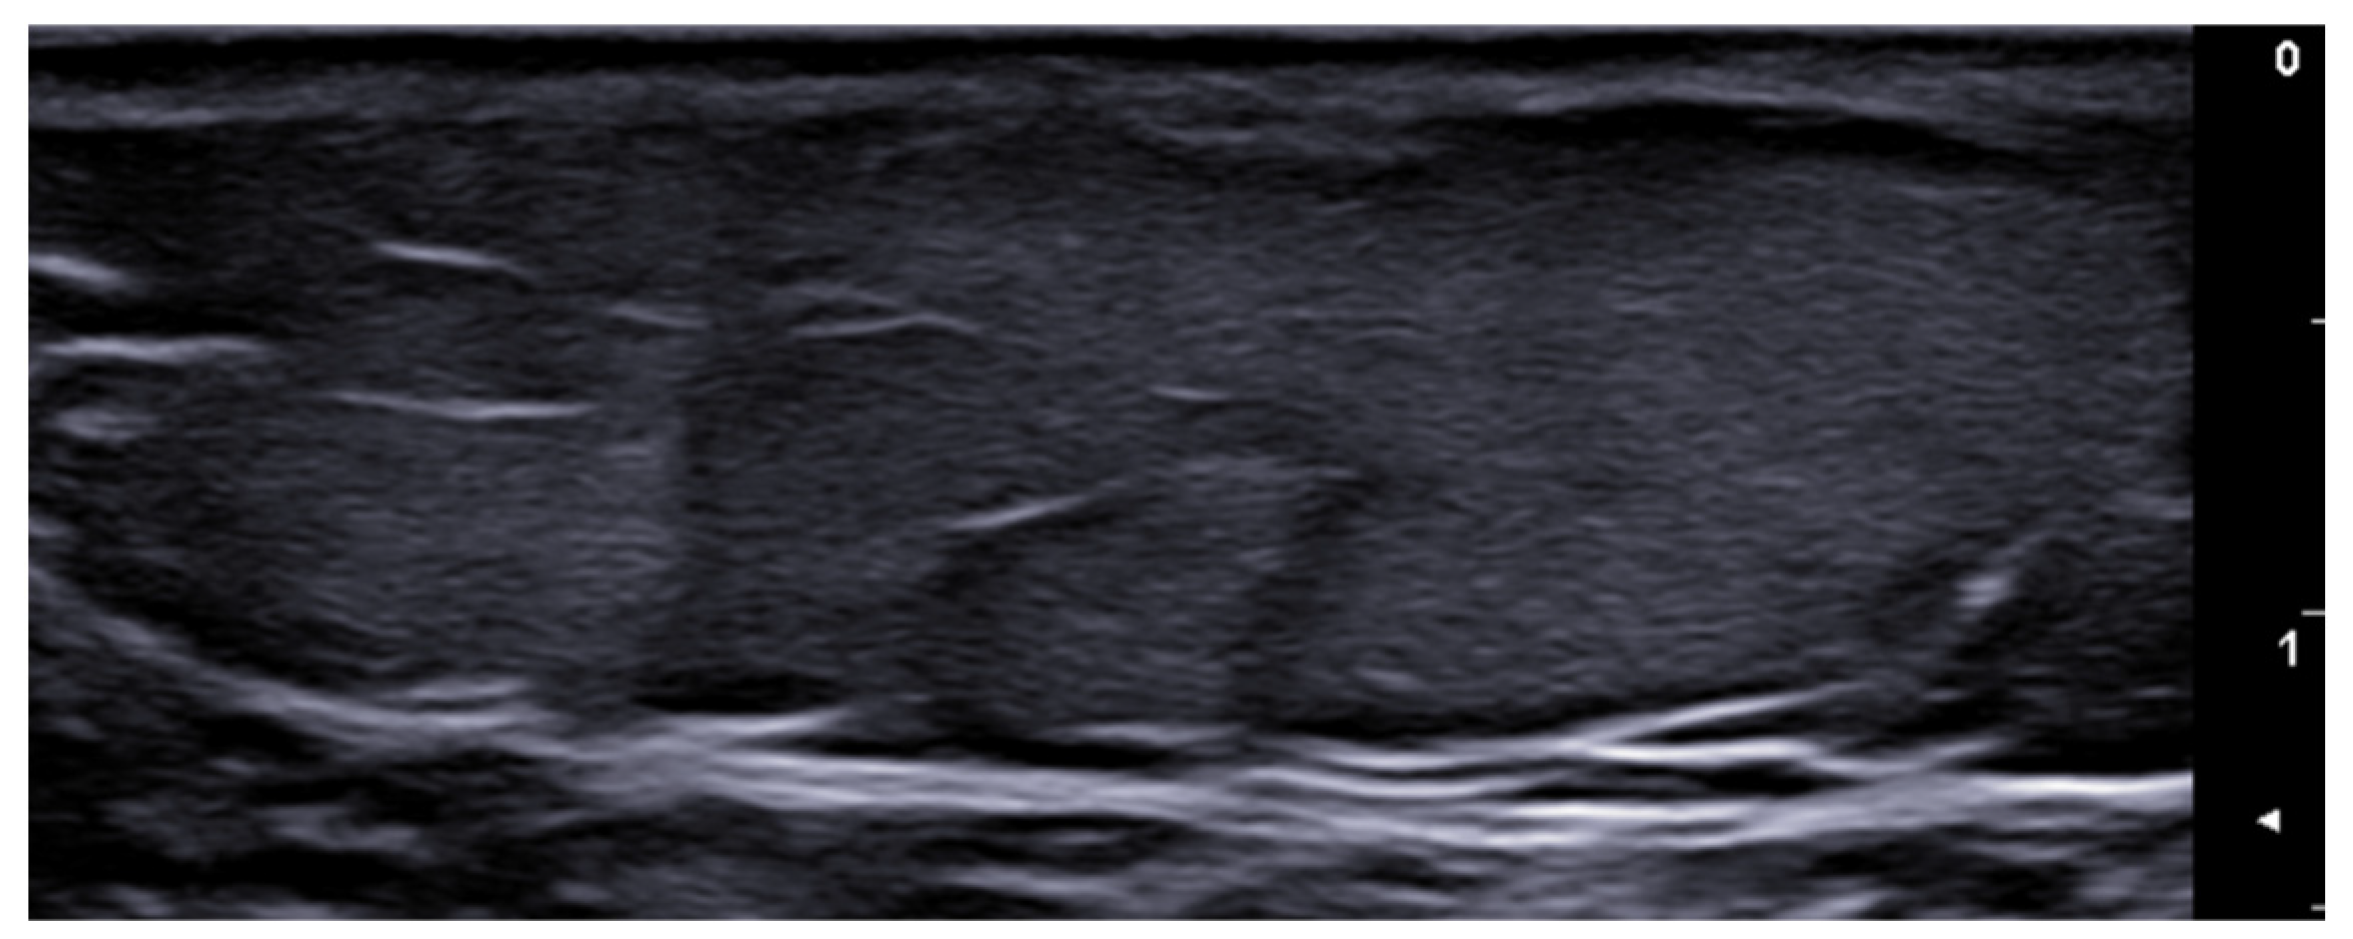

- Michelucci, A.; Dini, V.; Salvia, G.; Granieri, G.; Manzo Margiotta, F.; Panduri, S.; Morganti, R.; Romanelli, M. Assessment and Monitoring of Nail Psoriasis with Ultra-High Frequency Ultrasound: Preliminary Results. Diagnostics 2023, 13, 2716. [Google Scholar] [CrossRef]

- Sechi, A.; Starace, M.; Piraccini, B.M.; Wortsman, X. Ultrasound Features of Onychopapilloma at High-Frequency and Ultra-High Frequency. J. Ultrasound Med. 2024, 43, 71–76. [Google Scholar] [CrossRef] [PubMed]

- Turner, V.L.; Wortsman, X. Ultrasound Features of Nail Lichen Planus. J. Ultrasound Med. 2024, 43, 781–788. [Google Scholar] [CrossRef]